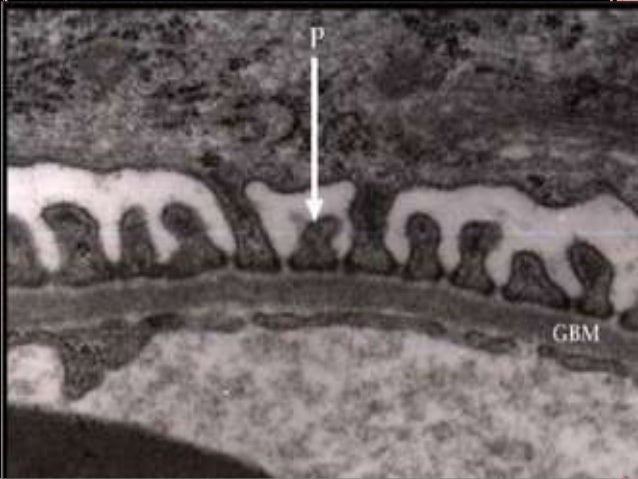

5. 5. RINS - FUNÇÕES 5 Filtração sanguínea;  Conservação dos metabólitos essenciais;  Secreção dos produtos residuais. Controlam o equilíbrio ácido-básico; Órgão endócrino – eritropoetina e renina.

13. 13. NÉFRONS - HISTOLOGIA Podócitos  Células do folheto visceral;  Tecido epitelial simples pavimentoso;  Aderidas à membrana basal dos capilares glomerulares. 13